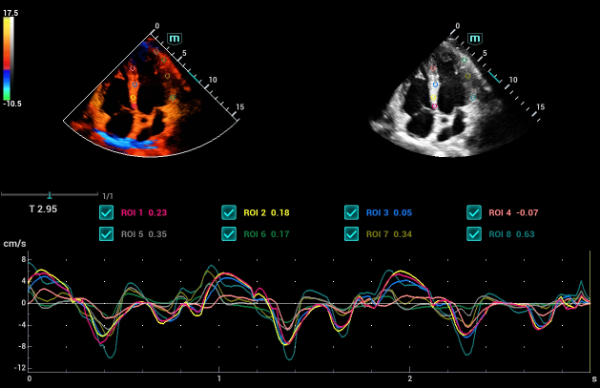

Bez wzgl?du na to, czy pracujesz w szpitalu, przychodni, czy u?ywasz ultrasonografu do badaÅ ogÃģlnych, w opiece zdrowotnej kobiet lub w badaniach sercowo-naczyniowych, w serii Consona znajdziesz bardzo pot??ne narz?dzia, aby utrzyma? si? w czo?Ãģwce.

Galeria obrazÃģw